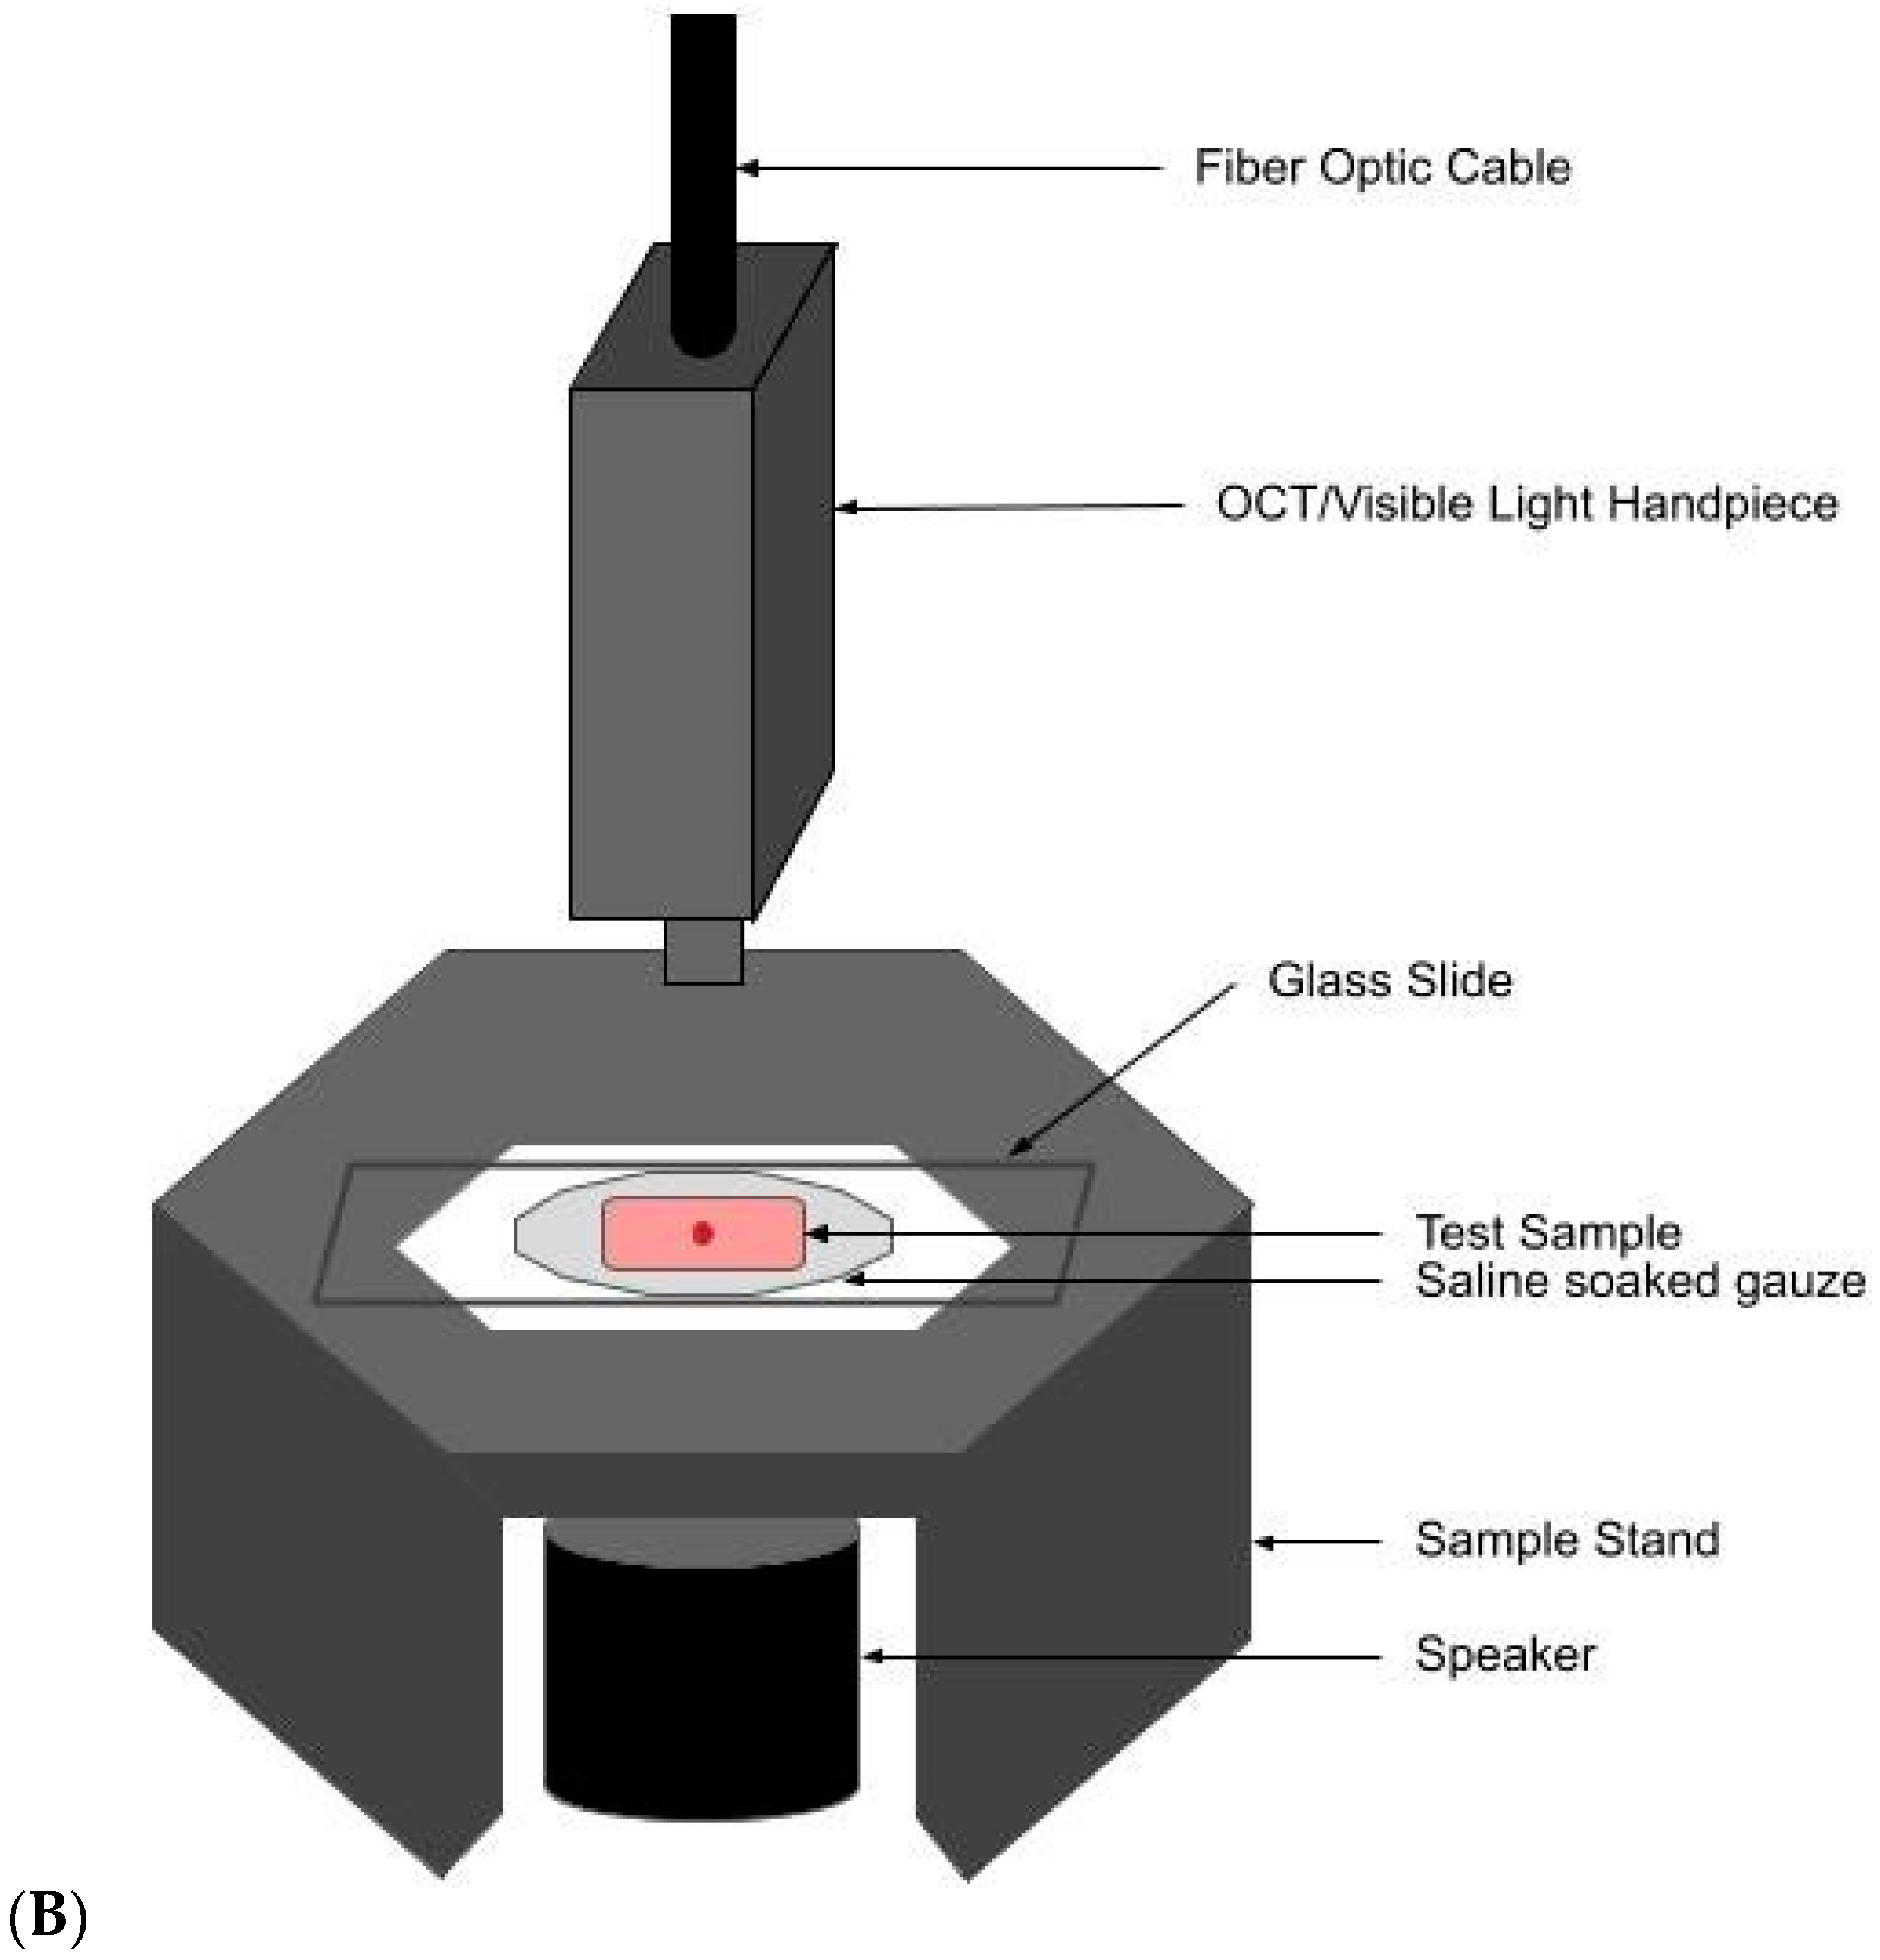

2.2. OCT Images and Scans of Pixel Intensity Versus Depth Measurements

3. Results

4. Discussion

4.1. The 80 Hz Peak

4.2. The 130 Hz Peak

4.3. The 260 Hz Peak